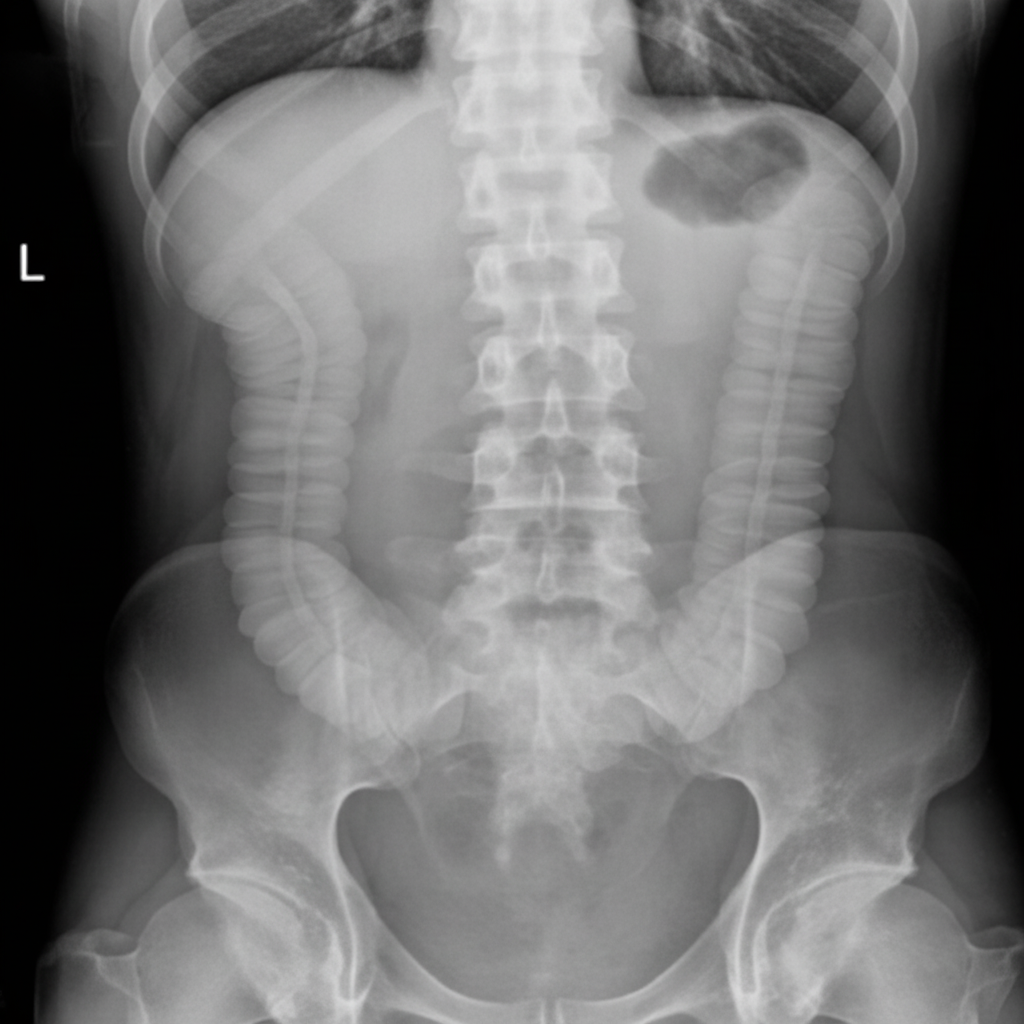

The given image shows findings most consistent with which of the following conditions?

Explanation: ***Ischemic colitis*** - The image demonstrates classic **"thumbprinting"** sign on plain X-ray, characterized by **mucosal edema** and **submucosal hemorrhage** creating rounded protrusions into the colonic lumen. - **Ischemic colitis** typically affects the **splenic flexure** and **sigmoid colon** in elderly patients, showing **wall thickening** and loss of haustral markings. *Ileal atresia* - Presents with **multiple dilated small bowel loops** on X-ray, typically in **newborns** with **bilious vomiting**. - Shows **absence of gas** in the distal bowel beyond the point of atresia, not the thumbprinting pattern seen here. *Meconium ileus* - Radiologically shows **soap bubble appearance** in the **right lower quadrant** due to **inspissated meconium** mixed with air. - Associated with **cystic fibrosis** in neonates, presenting with **small bowel obstruction** without the colonic changes observed. *Crohn's disease* - Demonstrates **"string sign"** on imaging due to **strictures** and **skip lesions** affecting the **terminal ileum** predominantly. - Shows **cobblestone appearance** with **deep ulcerations** and **fistula formation**, distinct from the acute thumbprinting pattern.